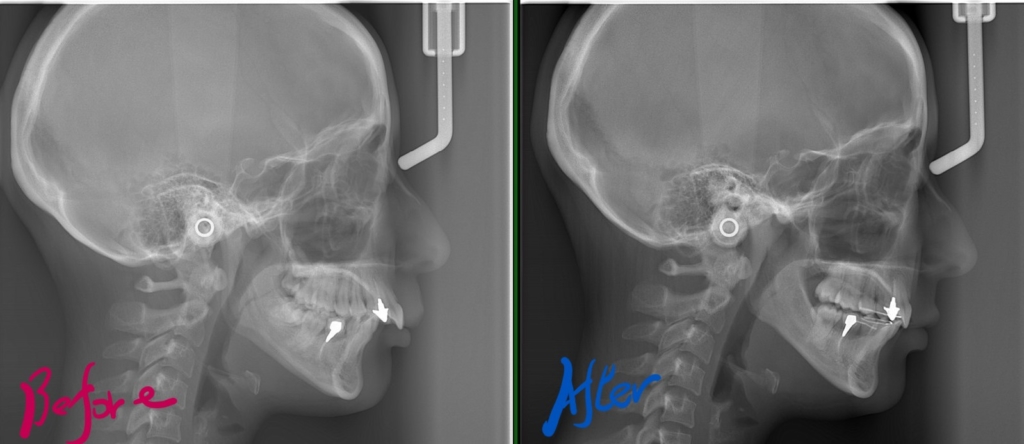

レントゲン写真で確認すると、

この患者さんの場合、

矯正後の状態をレントゲン写真で確認すると、

矯正治療の結果、上の前歯が引っ込んで鼻唇角が開いて大きくなり、上唇辺りにあったボテッとした感じも無くなりました。 また、上の前歯により下へ押されて90度屈曲してた下唇も伸びました。 結果として口元を非常にスッキリさせることが出来たように思います。

参考までに、矯正治療の前後を比較してみましょう。

まずはレントゲン写真からです。